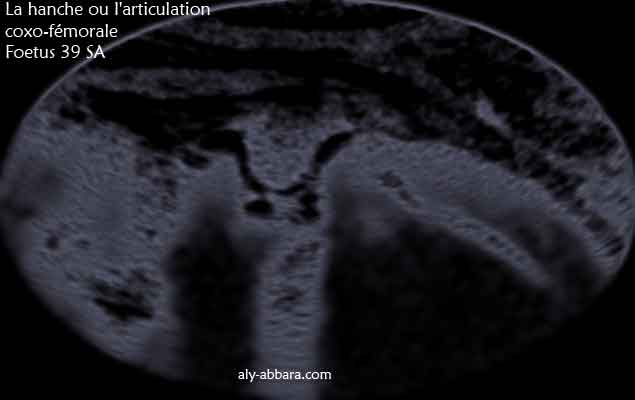

Image échographique en négatif montrant les éléments anatomiques composant la hanche ou l'articulation coxo-fémurale (la tête de la fémur et la cavité de l'acétabulum "acétabule").

Fœtus de 39 SA d'âge.